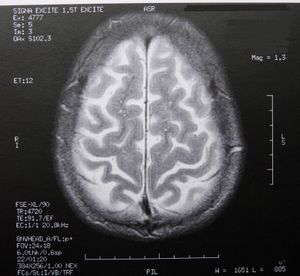

Gehirn: MRT-Scans zeigen Veränderungen (Foto: pixelio.de, Dieter Schütz) |

Guangzhou (pte025/05.04.2016/10:30) Forscher des Department of Medical Imaging, Guangdong No. 2 Provincial People's Hospital http://bit.ly/1MPrvbc haben mittels MRT-Scans bei Patienten mit Schlaflosigkeit Anomalien in der weißen Hirnsubstanz nachgewiesen. Bei einer primären Insomnie fällt es den Betroffenen mehr als einen Monat lang entweder schwer, einzuschlafen oder durchzuschlafen. Tagesmüdigkeit, Stimmungsschwankungen und kognitive Einschränkungen sind die Folgen. Aber auch Depressionen sind möglich.

An der Studie nahmen 23 Patienten mit primärer Insomnie und eine aus 30 Personen bestehende gesunde Kontrollgruppe teil. Zur Feststellung des geistigen Zustands und der Schlafmuster füllten alle Teilnehmer eine ganze Reihe von standardisierten Fragebögen wie dem Pittsburgh Sleep Quality Index aus, in denen unter anderem auch nach dem Auftreten von Depressionen gefragt wurde. Bei allen wurde auch mit der Diffusions-Tensor-Bildgebung ein MRT des Gehirns durchgeführt. Dieses Verfahren ermöglicht es, das Muster der Wasserbewegung entlang der Verbindungen der weißen Substanz sichtbar zu machen.

Mittels eines neuen Verfahrens, der Tract-Based Spatial Statistics, konnte nachgewiesen werden, dass die Patienten über eine deutlich verringerte Integrität in verschiedenen rechten Gehirnbereichen und dem Thalamus verfügten. Der Thalamus reguliert Bewusstsein, Schlaf und Wachheit. Die beeinträchtigen Bereiche der weißen Substanz stehen laut Li vor allem mit der Regulierung von Schlaf und Wachheit, der kognitiven Funktion und der sensomotorischen Funktion in Zusammenhang. Anomalien des Thalamus und des Corpus callosum, der größten Struktur weißer Substanz im Gehirn, standen mit der Dauer der Schlaflosigkeit und den Ergebnissen der eigenen Beurteilung von Depressionen in Verbindung.